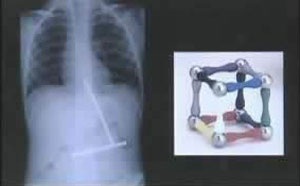

Bản phim chụp X quang dưới đây lại cho thấy một cậu bé đã nuốt những mảnh từ tính của một khối lập phương.